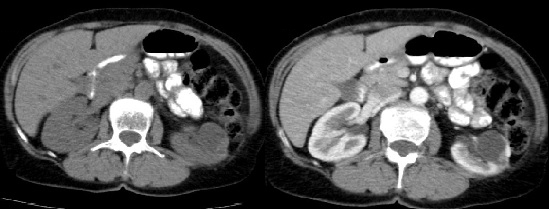

Fase nefrográfica o portal

Se logra a partir de los 80 a 180 segundos posteriores a la inyección del contraste; el medio de contraste se encuentra en los túbulos colectores y asa de Henle durante esta fase y su utilidad se basa en el aumento homogéneo del parénquima renal, lo que permite una mejor delimitación de la masa renal.

Durante esta fase se presenta el mayor realce de los tumores sólidos, por lo que se logra una mejor caracterización de las masas indeterminadas. En un estudio sobre la caracterización de las masas renales menores a 3 cm se concluyó que durante las exploraciones en fase nefrográfica se permitió una mayor detección de lesiones y una mejor caracterización de las masas renales pequeñas que en las exploraciones de fase corticomedular 3-5 (Fig. 3).